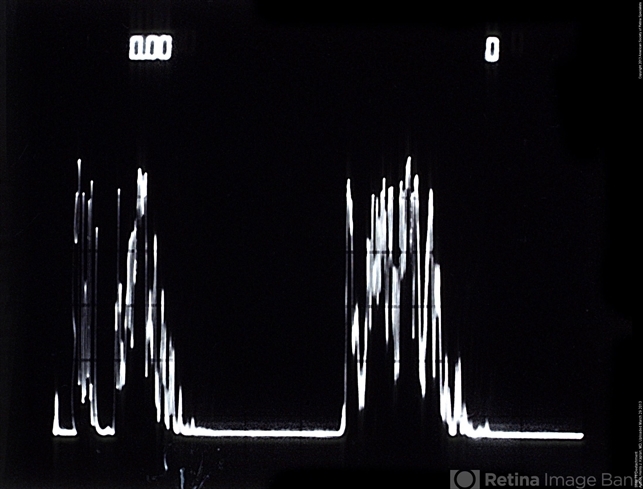

- A-scan ultrasound

- Typical A-scan spikes of high internal reflectivity in choroidal hemangioma.